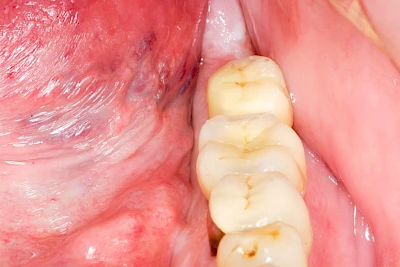

Knochenaufbau und Implantateinsatz

Ist nicht genügend Knochen zur Verankerung eines Implantates vorhanden, kann über einen sogenannten Knochenaufbau die Möglichkeit für das Einbringen eines Implantates geschaffen werden. Dazu kann z. B. Knochen aus der Kieferwinkelregion oder auch aus der Kinnregion entnommen und im Bereich der Fehlstellen aufgetragen werden. Auch künstliches Knochenmaterial kann dabei zum Einsatz kommen.

Im Oberkiefer wird – wenn ein Knochenaufbau notwendig ist – der Knochen in der Regel nicht außen "aufgelegt", sondern es wird der Boden der Kieferhöhle entweder über den Implantat-Bohrkanal durch Verdichtung nach oben gedrückt (interner Sinuslift) oder über eine Fensterung der vorderen knöchernen Kieferhöhlenwand kann Knochen im Bereich des Kieferhöhlenbodens eingebracht (externer Sinuslift).

Knochenaufbau im Unter- und Oberkiefer